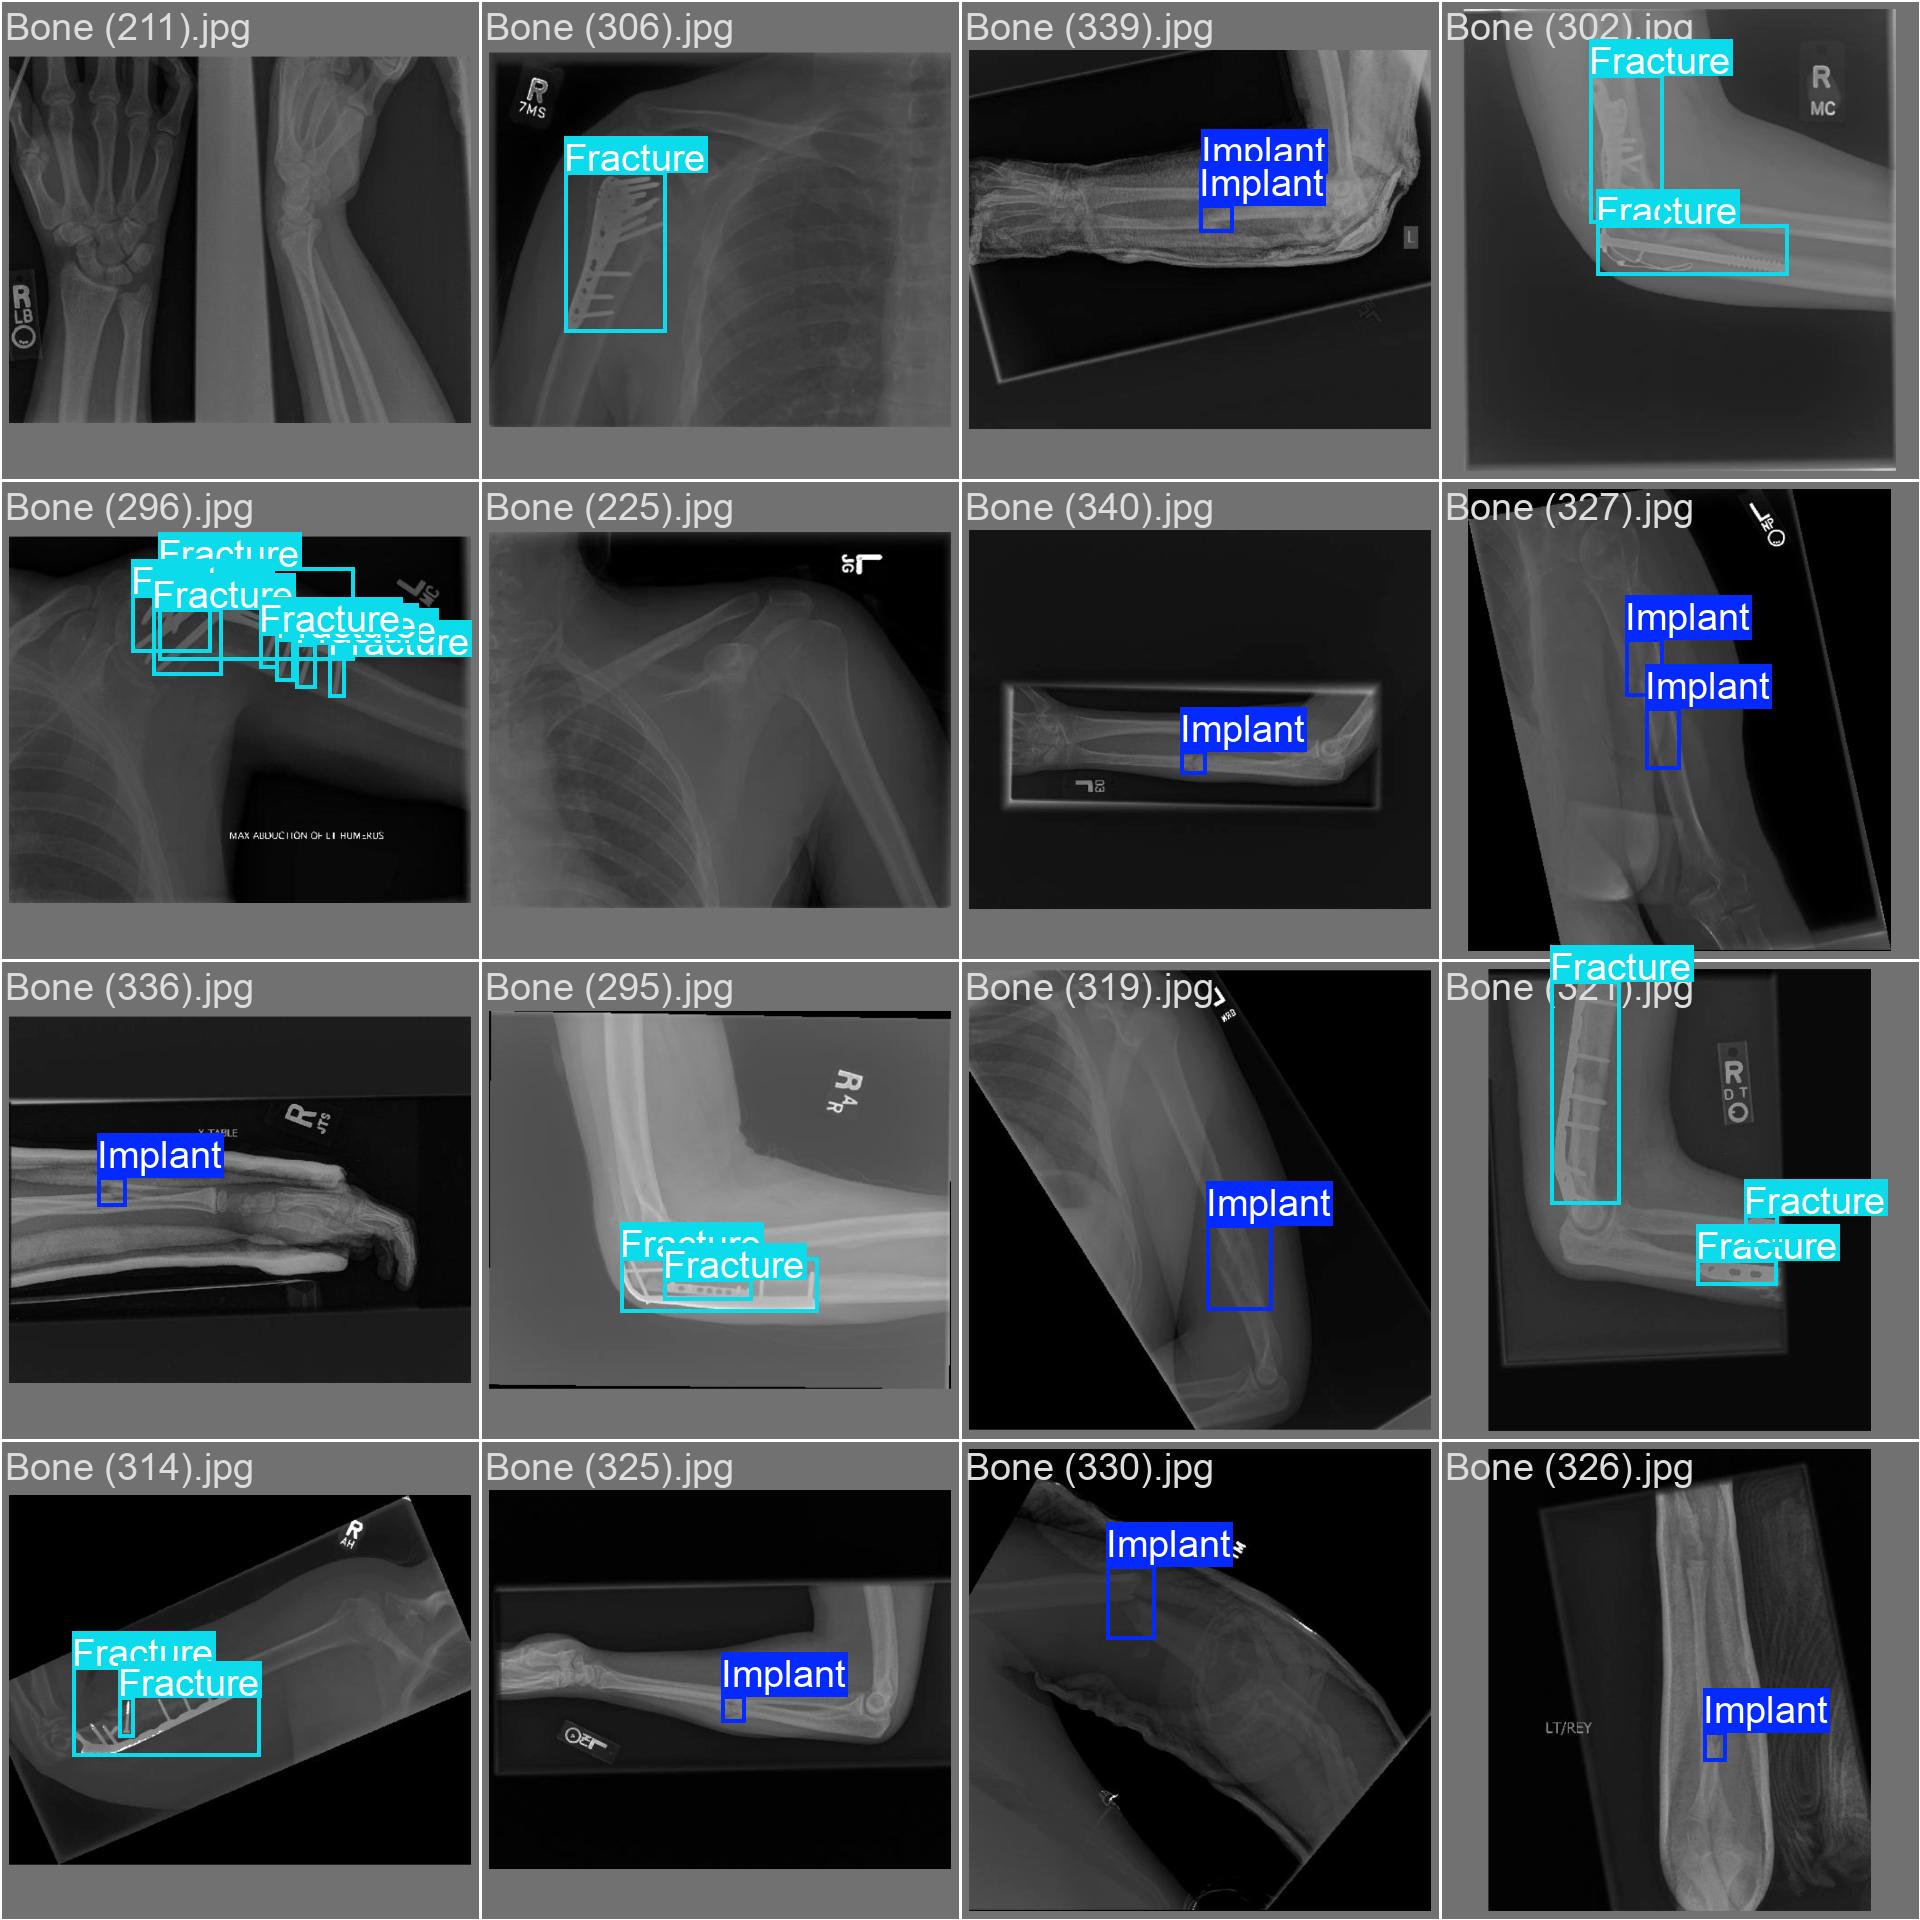

20251204_01 predict

class 이름을 반대로 해뒀다...

| imgsz | 800 | 뭔가 train이랑 같아야할 것 같아서 같이 바꿨다 |

| conf | 0.3 | 원래 0.9였는데 어제 결과가 너무 안 나와서 0.5로 바꿨다가 다시 0.3으로 바꿨다 |

20251204_02 predict2

진짜 라벨링 문제였나보다